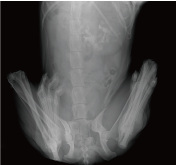

Application